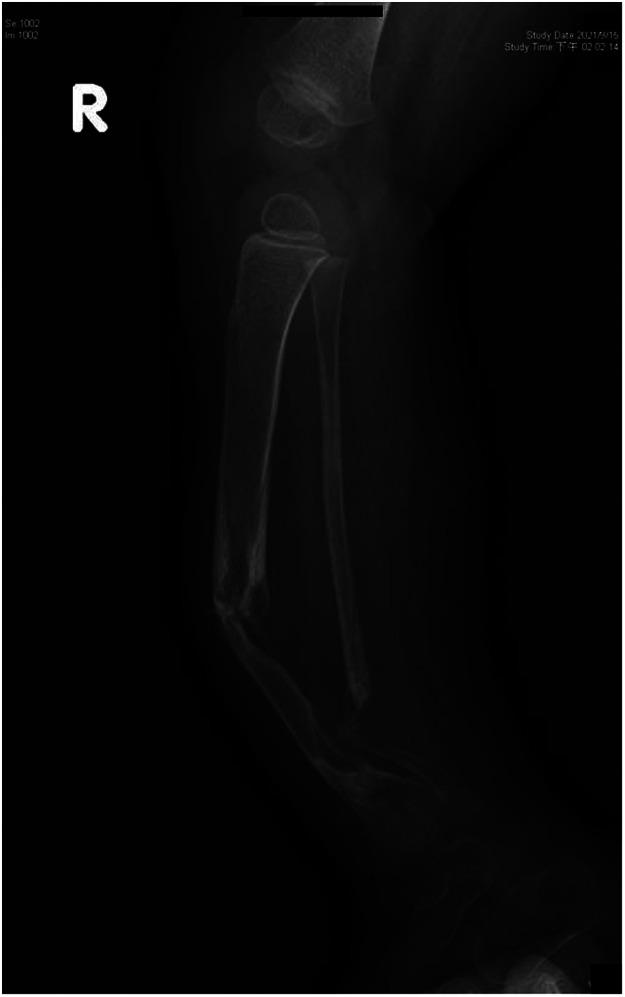

Congenital pseudoarthrosis of the tibia (CPT) is a rare pathological disease associated with neurofibromatosis type 1 (NF1). It presents with tibial bowing and can progress into a nonhealing fracture. Treatment options include conservative approaches such as serial bracing or various surgical options.Surgically, the aims are to achieve long-term bone union, prevent limb length discrepancies (LLDs), and avoid mechanical axis deviation, soft tissue lesions, nearby joint stiffness, and pathological fracture.The purpose of our study is to highlight our experience with both the conservative approach and the use of vascularized free fibula reconstruction of these deformities, including the challenges encountered with a long-term follow-up until skeletal maturity.

We present a retrospective analysis of a total of nine (9) patients consisting of three (3) girls and six (6) boys. Six (6) children were treated with a vascularized fibula flap, and the other three (3) were treated conservatively. Outcomes measured included fractures, LLD, ankle valgus deformity, donor site morbidity, and number of surgical corrections.

All patients had flap survival. Three (3) of six children had a previous failed surgery with intramedullary nail and bone graft prior to performing a vascularized free fibula reconstruction. The follow-up period ranged from 8 months to 200 months. The complications included stress fractures (50%), LLD (66.6%), and ankle valgus (33.3%). During growth phases, these children required multiple corrective surgeries.